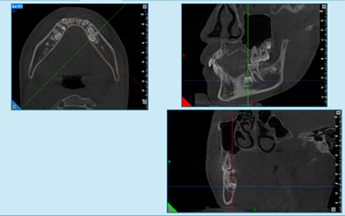

图4 三维断层截图,标线交叉处为左侧下颌骨埋伏多生牙1

图5 三维断层截图,标线交叉处为左侧下颌骨埋伏多生牙2

图6 三维断层截图,标线交叉处为右侧下颌骨埋伏多生牙1

图7 三维断层截图,标线交叉处为右侧下颌骨埋伏多生牙2